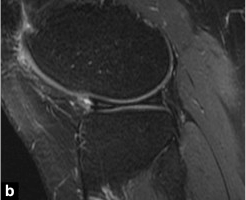

Наиболее частой находкой является прямая визуализация мигрирующих отломков в межмыщелковой области: ориентир «двойной задней крестообразной связки (ЗКС)» характерен при повреждении медиального мениска и интактности передней крестообразной связки.Вывихнутый сегмент выглядит как дугообразная гипоинтенсивная полоса, параллельная нормальной задней крестообразной связке, создавая вид «двойной ЗКС» (рис. 7).Избыточные грабельные рожки (размером более 6 мм) также могут свидетельствовать о наличии рукоятки ствола (рис. 8).В этом случае вывихнутый фрагмент мениска прикрепляется к здоровому переднему рогу.

Рисунок 7 Внешний вид рукоятки медиального мениска имеет признак «двойной ЗКС».Сагиттальный PD-взвешенный вид с подавлением жировой ткани: смещенный фрагмент мениска (стрелка) лежит ниже нормальной ЗКС (стрелка) и образует характерный вид «двойной ЗКС».